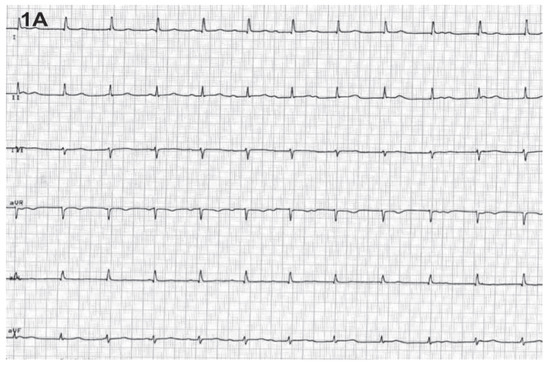

A 59-year-old man with severe mitral regurgitation underwent successful mitral valve repair. Postoperative recovery was uneventful except for the development of a third-degree atrio-ventricular block (fig. 1A). The haemodynamic consequences of the atrio-ventricular dissociation were observed during echocardiography (fig. 1B and fig. 1C): at the beginning and the end of the re- cordings, right atrial depolarisation and contraction occurs during ventricular systole when the tricuspid valve is closed, leading to reversal of blood flow (short arrows). This echocardiographic finding represents the clinically observable jugular venous pulsation called “Cannon waves”. In contrast, when the atrio-ventricular sequence is more or less correct, the backflow into the IVC and the HV is minimal (long arrows).

Figure 1A. Third-degree atrio-ventricular block.